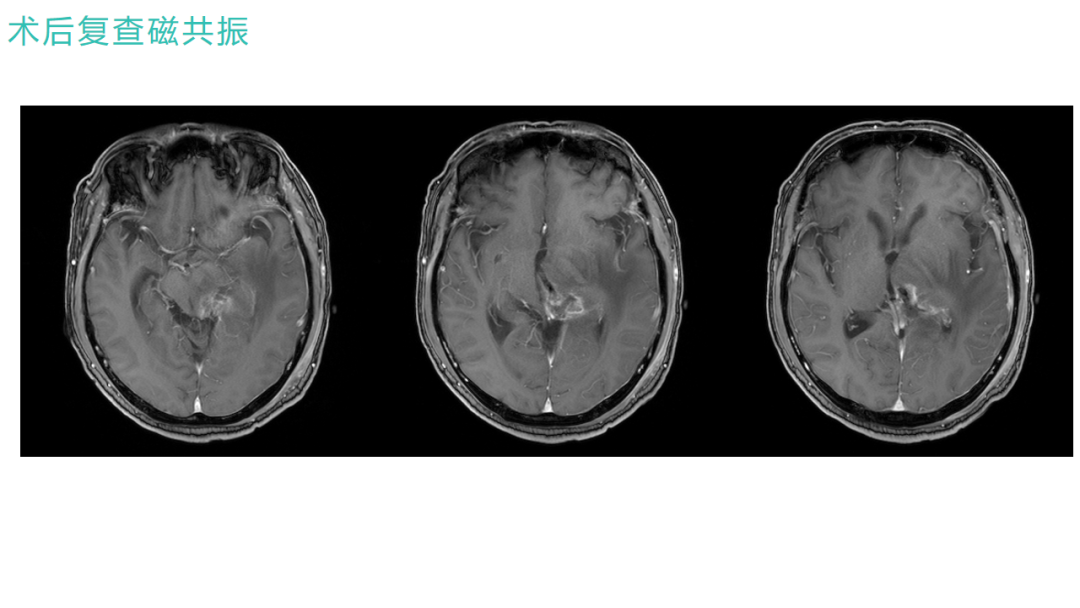

术后情况

术前右侧偏瘫行走不能,术后第6天下床行走

2024年9月5日